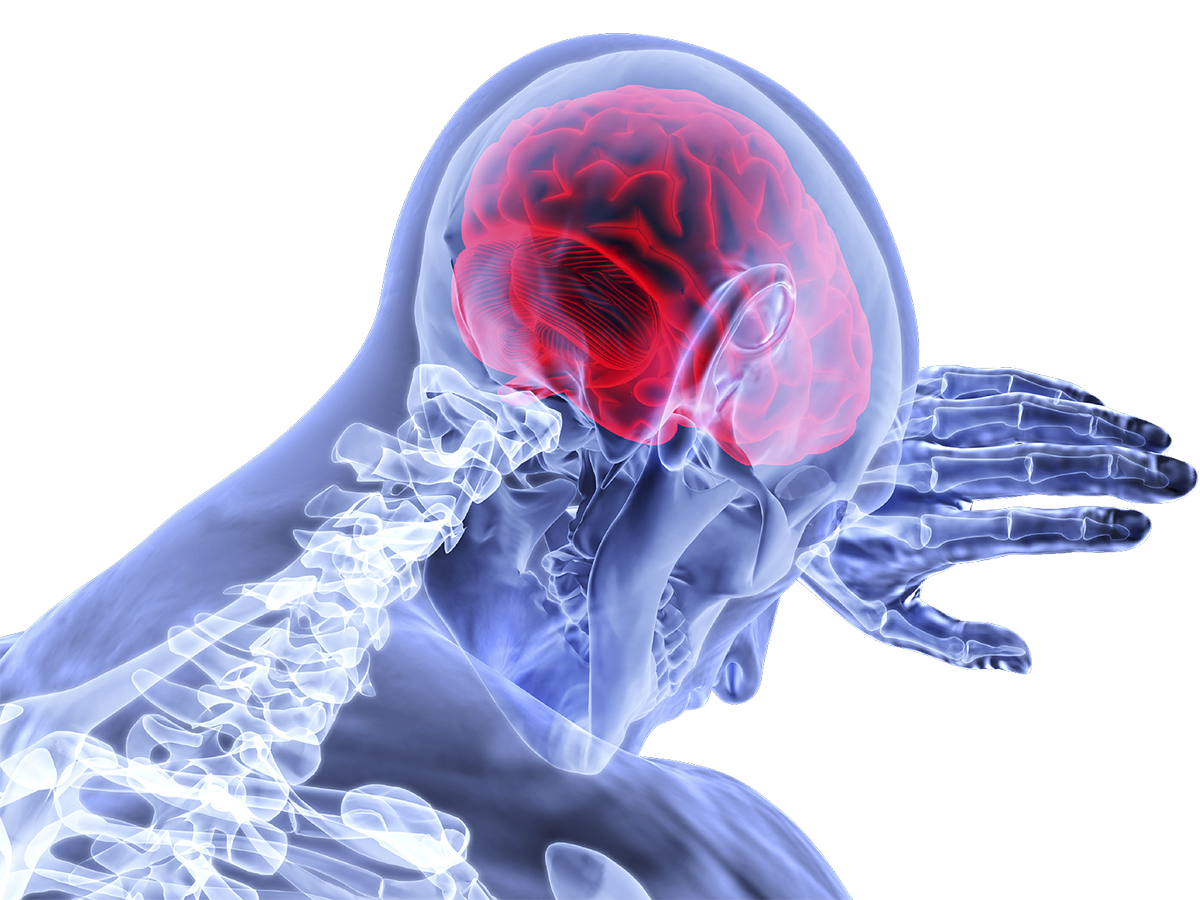

Онколог назвал основные симптомы опухоли мозга

Эксперт Российского общества клинических онкологов Григорий Кобяков рассказал об основных признаках развития злокачественной опухоли мозга. По его словам, можно выделить два типа симптоматики: общемозговая и неврологическая.

В первом случае наблюдается головная боль, возможно, с тошнотой и рвотой, снижение уровня бодрствования или нарушение сознания. Во втором — у больного происходит нарушение движений в противоположных пораженному полушарию руке и ноге, его речь затруднена, ухудшается память, угол зрения сужается.